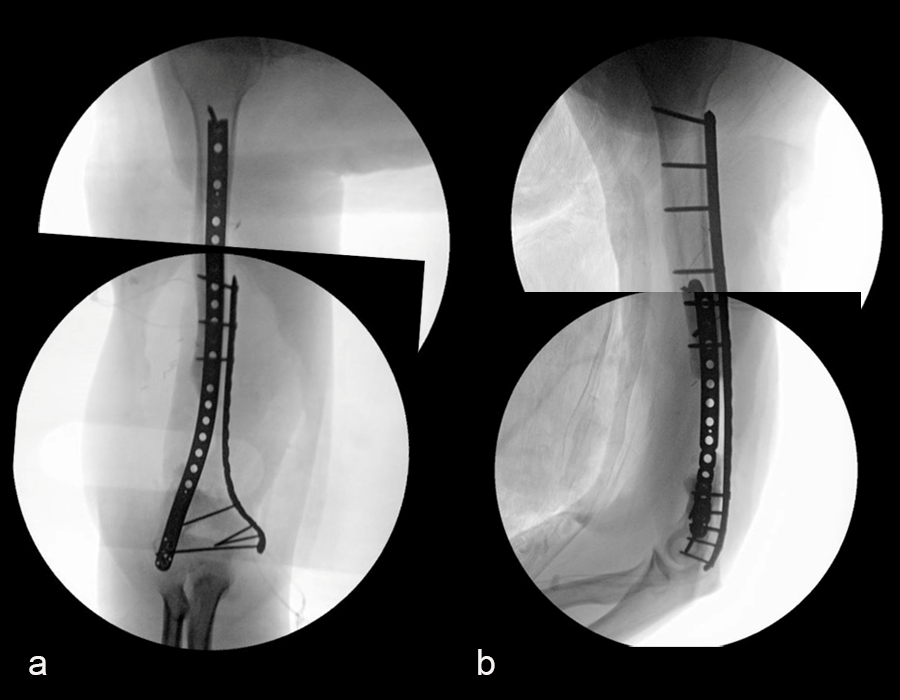

In a first stage, the distal humerus was debrided and devitalized bone was resected, leaving an 8cm defect into which a cement spacer was placed. New plates were inserted to stabilize the fracture (Fig 17 and Fig 18). Cultures taken in the OR were negative.

In October 2022, planning began for the second stage of surgery. A graft cage was planned (Fig 19) to allow the formation of new bone in the 8cm defect.

The second stage of surgery took place in October 2022. The cage was inserted (Figs 20-22) and filled with ~20cc autograft obtained by RIA of the femur, 30cc allograft and 3cc BMAC.